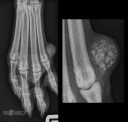

RadioQuiz 19 – Petite masse sur un pied